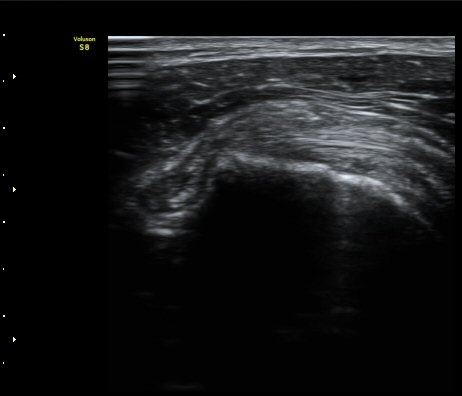

ÁÖ»ç ÈíÀΰú Á¡¾×³¶³» ÁÖ»çÄ¡·á(÷ºÎ ÆÄÀÏ) 1ÀÏ ÈÄ ½ÃÇàÇÑ °Ë»ç¿¡¼­ Á¡¾×³¶ÀÇ ºÎÁ¾ ¹× ¼®È¸ÀÇ

Á¦°Å°¡ °üÂû µÊ(±×¸² 6, 7).